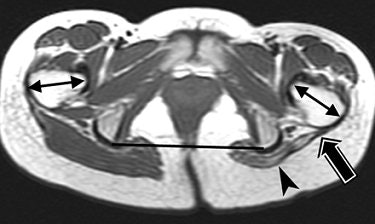

| Same patient as above. Spin-echo T1-weighted axial image (566/16) inferior in relation to image above discloses atrophic left gluteus maximus muscle (arrowhead), thickening and retraction of distal tendon and iliotibial tract (black arrows) posterior to left femur. Angle formed by lines of connecting ischia (black line) and axis of femoral necks (double-headed arrows) measures 9° on right side and 36° on left side. Exaggerated anteverted axis of left femoral neck suggests external rotation of left proximal femur. Chen CKH, Yeh L, Chang W, Pan H, and Yang C, "MRI Diagnosis of Contracture of the Gluteus Maximus Muscle," (AJR 2006; 187:W169-W174). |

The group concluded that the severity of the clinical abnormality can be judged by the presence of thickening and retraction of the fibrotic cord on MRI. In more advanced cases, a depressed groove will appear at the muscle-tendon junction, they added.